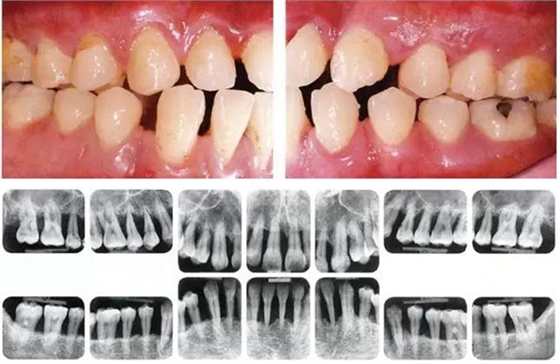

●49歲女性 慢性牙周炎(輕度)的口腔內(nèi)照片

49歲女性,接受過口腔衛(wèi)生士指導(dǎo),觀察發(fā)現(xiàn)頰舌側(cè)無菌斑,鄰接面有菌斑附著。牙周探診結(jié)果為全頜牙周袋深為3-4mm,同時(shí)拍攝口腔X片可觀察到全頜有輕度骨吸收。根據(jù)以上檢查、診查結(jié)果診斷出該患者為慢性牙周炎廣泛型(輕度)。視診觀察無牙齦腫脹、發(fā)紅等炎癥,觀察推斷可能是刷牙用力過度造成頰側(cè)牙齦萎縮。

●45歲女性 慢性牙周炎(重度)口腔內(nèi)照片

45歲女性,曾經(jīng)接受過口腔衛(wèi)生指導(dǎo)和牙周治療,菌斑控制情況除去部分磨牙部位其余基本良好。牙周探診檢查結(jié)果為全頜牙周袋深4~6mm,同時(shí)X片檢查數(shù)據(jù)可看到全頜重度骨吸收。根據(jù)以上檢查數(shù)據(jù)可診斷出該患者為慢性牙周炎廣泛型(重度)。牙齦沒有嚴(yán)重浮腫,但可觀察到紅褐色腫脹。上頜前牙有前突。